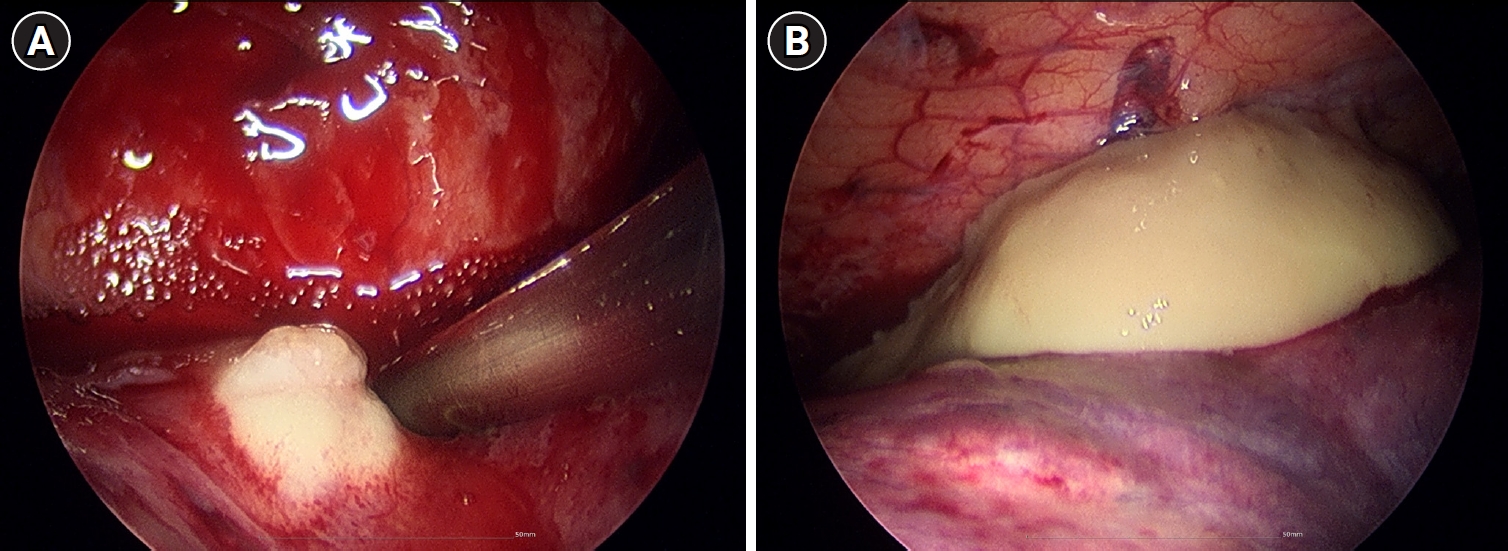

Empirical intravenous antibiotic therapy with piperacillin/tazobactam and levofloxacin was administered. On the second day of admission, the patient developed hemoptysis for which intravenous tranexamic acid was administered for 5 days, followed by oral maintenance. Clinical improvement was not achieved following a 7-day course of intravenous antibiotics, with the clinical course marked by unresolved febrile episodes and persistent leukocytosis. Furthermore, a follow-up chest CT on hospital day 7 revealed aggravation of the internal cavitations and abscess formation within the consolidative lesions of the right middle lobe and both lower lobes (Fig. 2). The failure of conservative management to arrest the necrotizing process, combined with the high risk of secondary sepsis from the poorly drained, inspissated purulent material, prompted the decision to escalate to video-assisted thoracoscopic surgery (VATS) for definitive source control and debridement. Intraoperative examination revealed dense pleural adhesions and extensive necrosis of the lung parenchyma. Thick, yellowish, and inspissated purulent material was drained from the abscess cavities located in the right middle and left lower lobes (Fig. 3). Given the deep and multiloculated nature of the abscesses, wide unroofing was performed via wedge resection using an endoscopic stapler and ultrasonic shear to ensure adequate drainage. Subsequently, thorough decortication and irrigation of the thoracic cavity were performed. A closed thoracostomy was performed with chest tube and Hemovac placement. Histopathological examination of the lung tissue revealed acute fibrinous and organizing pneumonia, consistent with chemical exposure.

Fig. 2.

Chest computed tomography on day 7 revealing multiloculated abscesses involving right middle and left lower lobes.

Fig. 2. Chest computed tomography on day 7 revealing multiloculated abscesses involving right middle and left lower lobes.